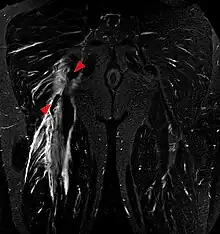

Imaging the hamstring muscles is usually performed with an ultrasound and/or MRI.[9] The biceps femoris is most commonly injured, followed by semitendinosus. Semimembranosus injury is rare. Imaging is useful in differentiating the grade of strain, especially if the muscle is completely torn.[10] In this setting, the level and degree of retraction can be determined, serving as a useful roadmap prior to any surgery. Those with a hamstring strain of greater than 60mm in length have a greater risk of recurrence.[11]